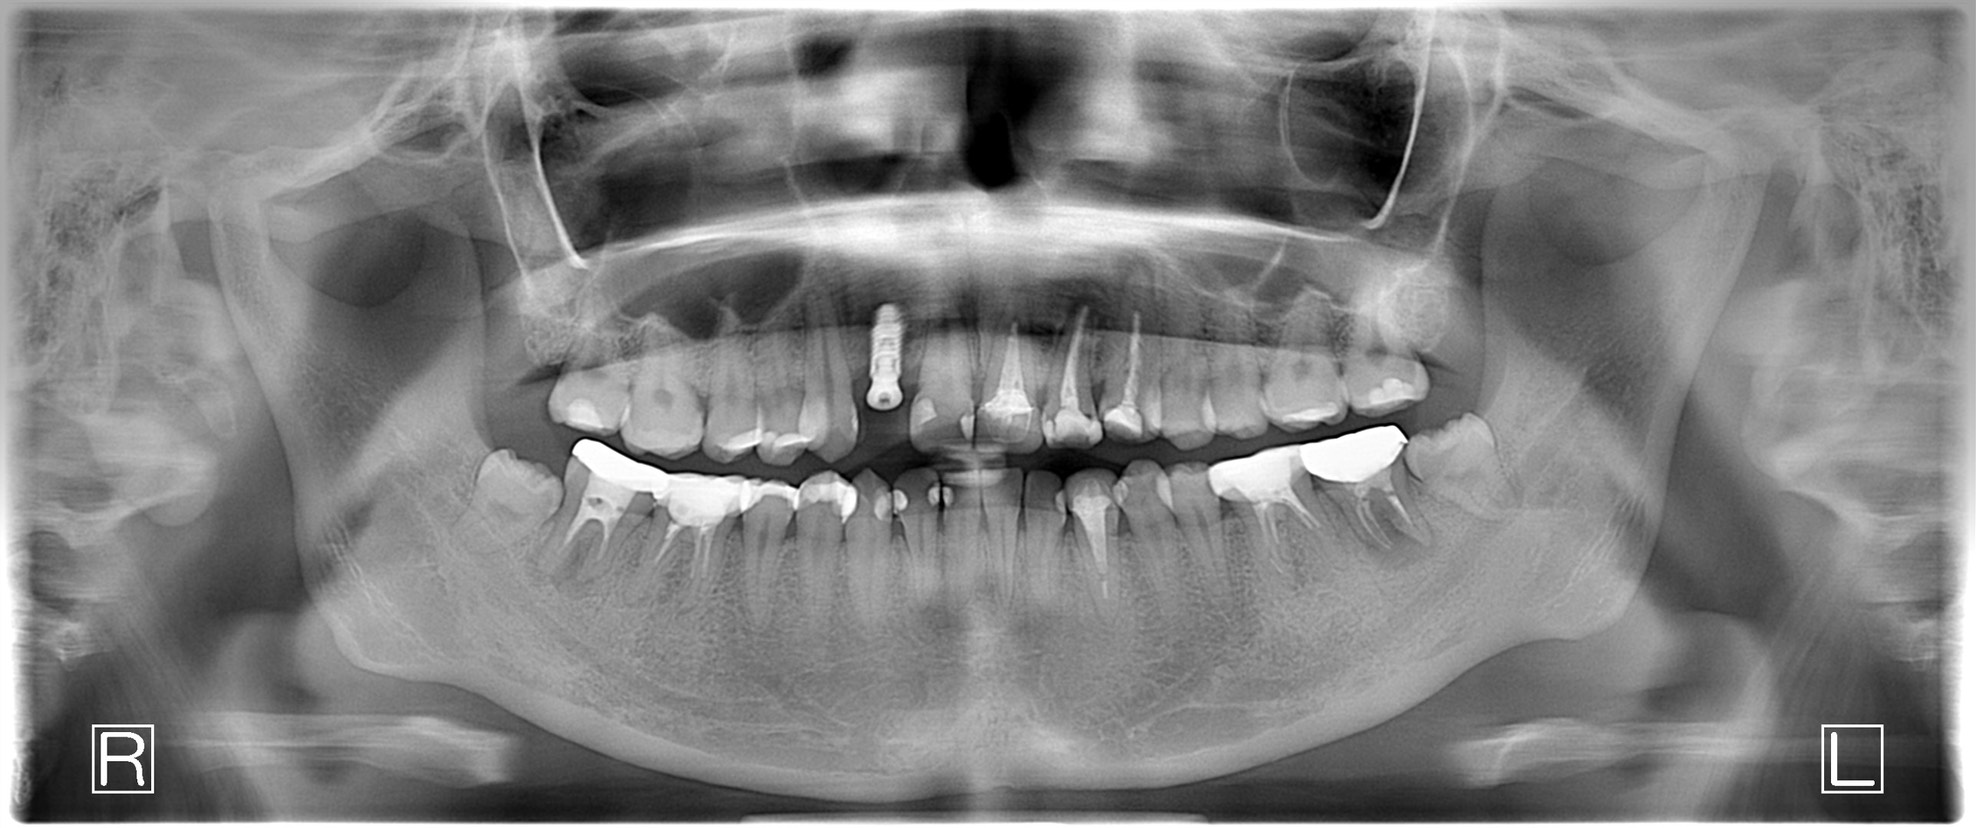

| 診断結果 | 右下7番歯根破折 |

| 治療内容 | 抜歯即時インプラント |